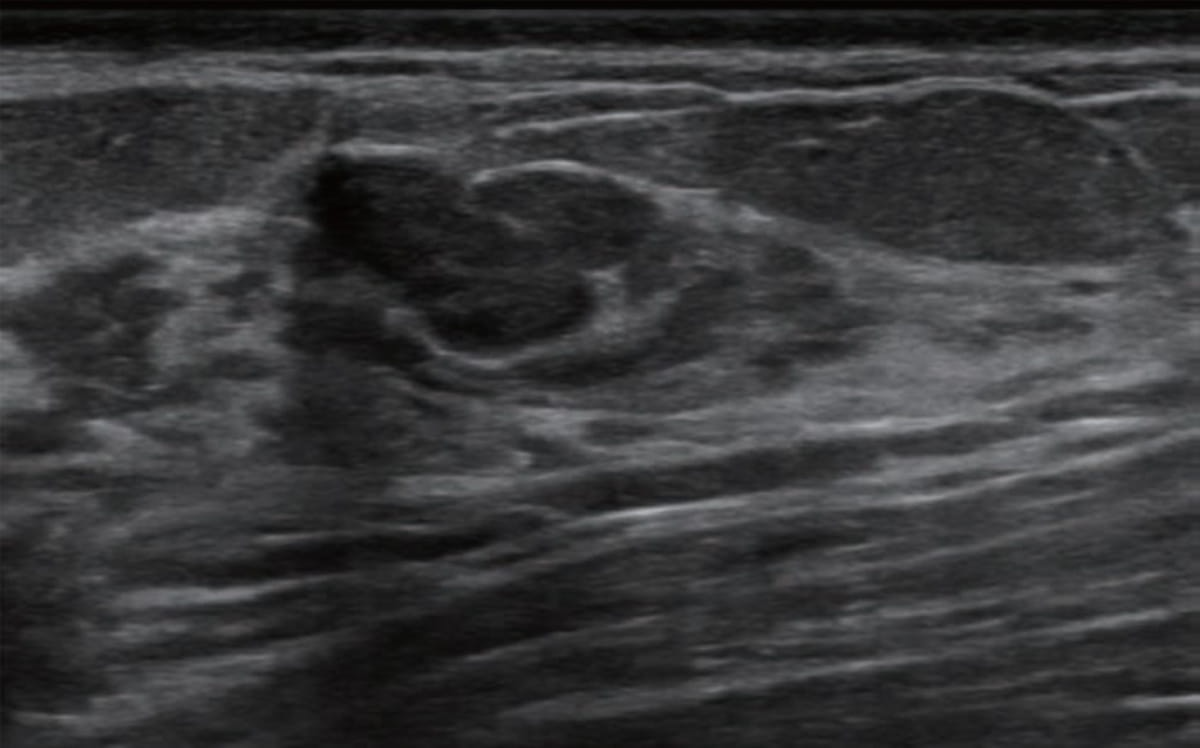

Emerging breast ultrasound research showed the use of computer-aided diagnosis (CAD), powered by deep learning, led to 24 percent and 36.9 percent improvements in accuracy and specificity, respectively, in the use of BI-RADS classifications by radiologists without breast ultrasound expertise.

Adjunctive use of an artificial intelligence (AI) software demonstrated nearly equivalent sensitivity and over 28 percent higher accuracy in comparison to radiologist assessment of breast ultrasound images for breast lesions, according to new research presented at the recent Society of Breast Imaging (SBI) conference.